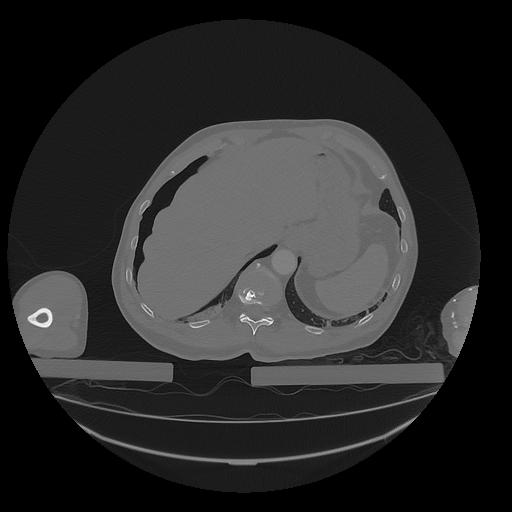

31 PULMON,CE,Vol,1.0,PULMON,,